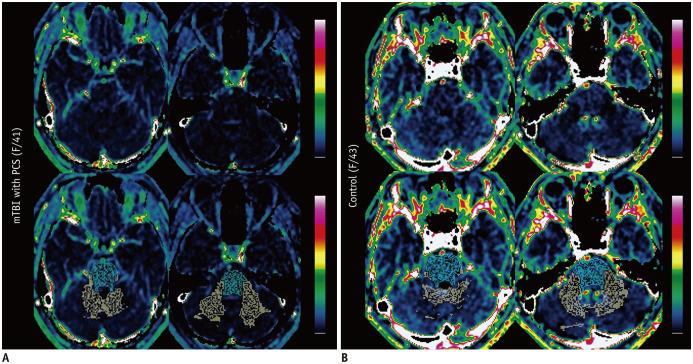

This study aimed to investigate the blood-brain barrier (BBB) disruption in mild traumatic brain injury (mTBI) patients with post-concussion syndrome (PCS) using dynamic contrast-enhanced (DCE) magnetic resonance (MR) imaging and automatic whole brain segmentation.

Forty-two consecutive mTBI patients with PCS who had undergone post-traumatic MR imaging, including DCE MR imaging, between October 2016 and April 2018, and 29 controls with DCE MR imaging were included in this retrospective study. After performing three-dimensional T1-based brain segmentation with FreeSurfer software (Laboratory for Computational Neuroimaging), the mean K and v from DCE MR imaging (derived using the Patlak model and extended Tofts and Kermode model) were analyzed in the bilateral cerebral/cerebellar cortex, bilateral cerebral/cerebellar white matter (WM), and brainstem. K values of the mTBI patients and controls were calculated using both models to identify the model that better reflected the increased permeability owing to mTBI (tendency toward higher K values in mTBI patients than in controls). The Mann-Whitney U test and Spearman rank correlation test were performed to compare the mean K and v between the two groups and correlate K and v with neuropsychological tests for mTBI patients.

RESULTS

Increased permeability owing to mTBI was observed in the Patlak model but not in the extended Tofts and Kermode model. In the Patlak model, the mean K in the bilateral cerebral cortex was significantly higher in mTBI patients than in controls ( = 0.042). The mean v values in the bilateral cerebellar WM and brainstem were significantly lower in mTBI patients than in controls ( = 0.009 and = 0.011, respectively). The mean K of the bilateral cerebral cortex was significantly higher in patients with atypical performance in the auditory continuous performance test (commission errors) than in average or good performers ( = 0.041).

CONCLUSION

BBB disruption, as reflected by the increased K and decreased v values from the Patlak model, was observed throughout the bilateral cerebral cortex, bilateral cerebellar WM, and brainstem in mTBI patients with PCS.